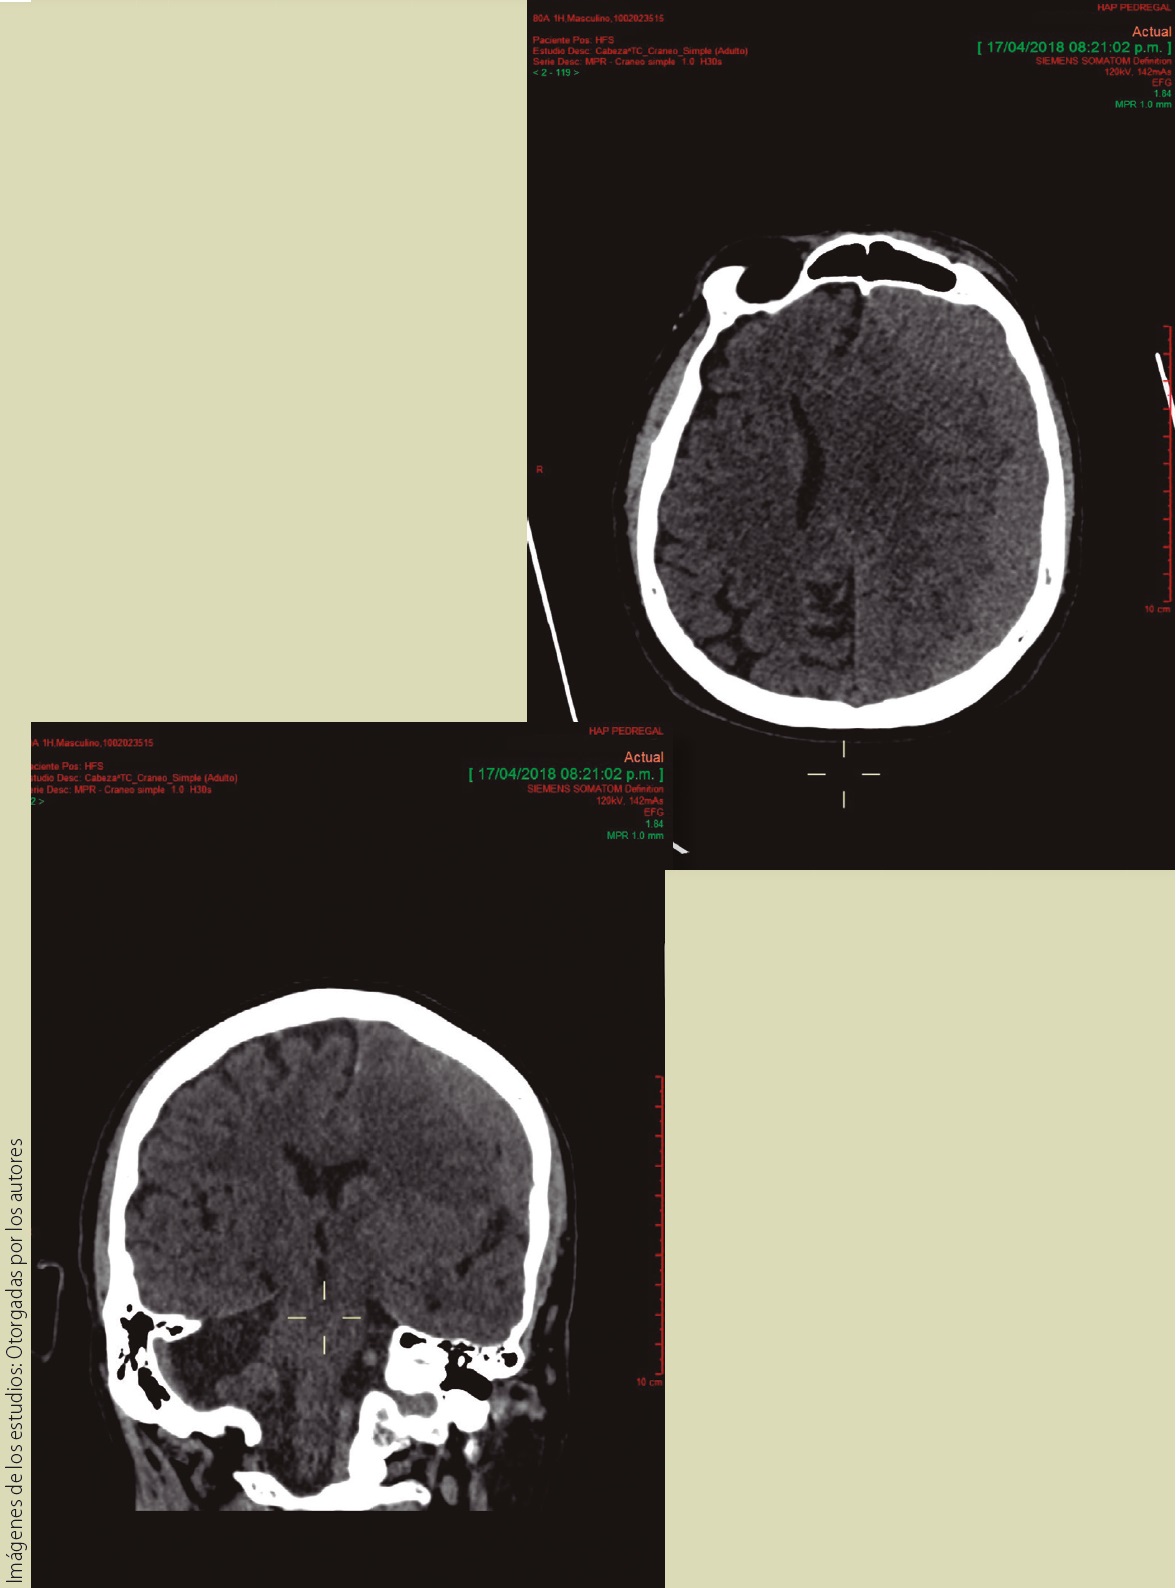

Paciente varón de 80 años quien hace 3 semanas sufrió caída de su propia altura; posteriormente inició con cefalea holocraneal y mareo, una semana después presentó desviación de la comisura labial y hemiparesia derecha.

1. ¿Qué método de estudio muestran las imágenes?

a) Radiografías de cráneo

b) Tomografía de cráneo simple

c) Tomografía de cráneo contrastada

d) Resonancia magnética

2. ¿El corte y reconstrucción mostradas corresponden a los planos?

a) Axial y coronal

b) Axial y sagital

c) Coronal y sagital

d) Coronal y oblicuo

e) Sagital y oblicuo

3. ¿Cuál es la morfología de la patología mostrada?

4. ¿La imagen mostrada corresponde a?

a) Hemorragia intrarventricular

b) Hemorragia parenquimatosa

c) Hematoma subdural

d) Hematoma epidural

e) Hematoma subgaleal

5. Con base en la respuesta anterior, ¿cuál es la definición del diagnóstico que presenta el paciente?

a) Desgarro de las venas subependimarias de la superficie de los ventrículos por extensión de hematoma parenquimatoso o hemorragia subaracnoidea.

b) Interposición de sangre por cizallamiento y disrupción de pequeños vasos perfornates.

c) Interposición de sangre entre la duramadre y la aracnoides como consecuencia del desgarro de los senos y venas corticales.

d) Interposición de sangre entre el periostio y la duramadre.

e) Acúmulo de sangre entre la aponeurosis epicraneal.